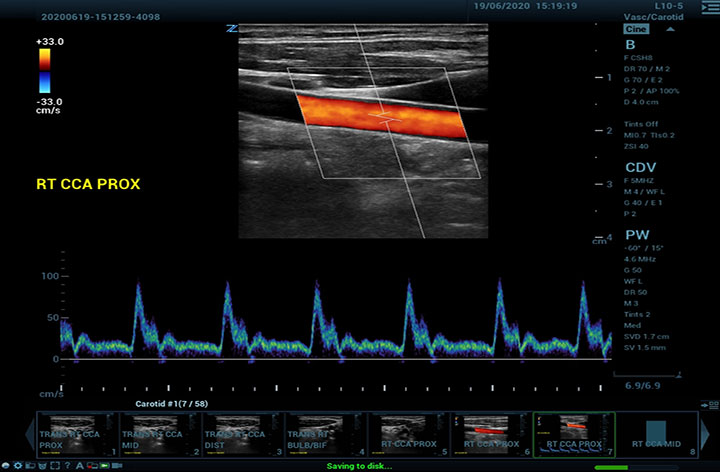

The Z.One PRO Ultrasound System Emerald Edition 2.0 is a powerful and portable advanced point-of-care imaging platform. Powered by software-based ZONE Sonography® Technology+ (ZST+), the Z.One PRO System provides optimal B-mode and Doppler imaging for patients, regardless of body habitus, helping ensure a reliable diagnosis. With a full family of transducers (from 2 – 20 MHz) and a wide range of applications, the Z.One PRO System is the imaging answer to your difficult clinical cases.